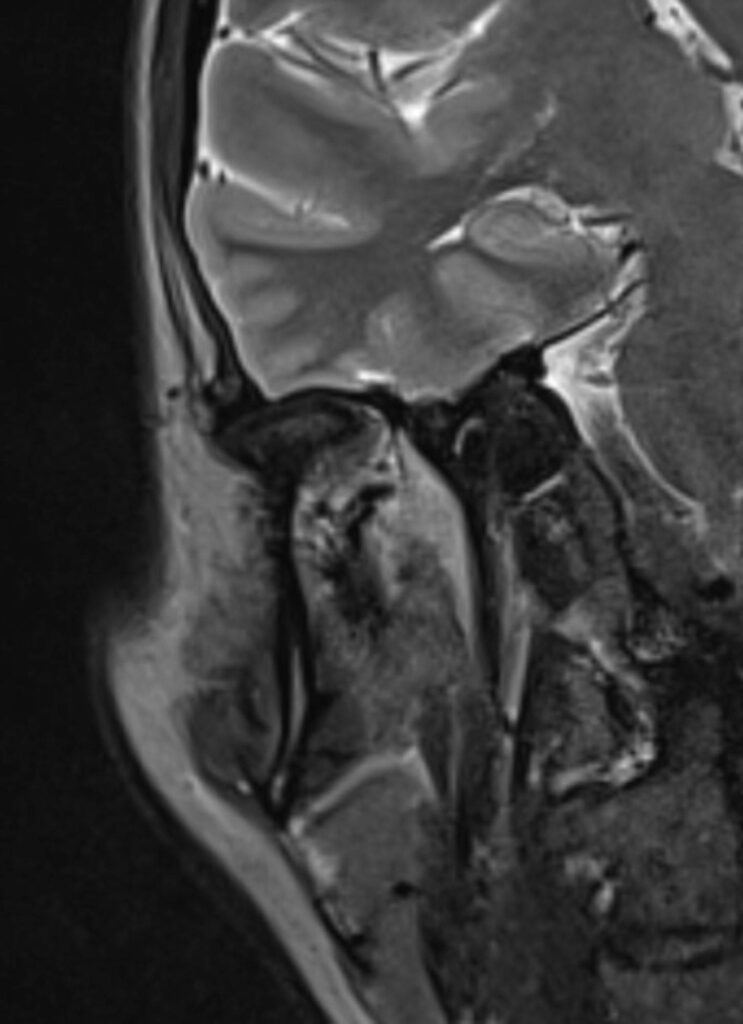

MRT Ohr

Wenn eine Beurteilung der Anatomie des Ohres mithilfe einer MRT-Untersuchung erfolgen soll, dann handelt es sich hierbei um eine MRT Kopf Untersuchung.

Was sieht man bei einer MRT Ohr?

Der große Vorteil der MRT liegt neben ihrer hohen Präzision im exzellenten Weichteilkontrast. Daher ist sie insbesondere bei der Beurteilung von Tumoren, Entzündungen und Nekrosen des Knochens und der Weichteile den übrigen bildgebenden Verfahren häufig deutlich überlegen. Selbst kleinste, sonst nicht sichtbare Veränderungen können oftmals per MRT sichtbar gemacht werden.